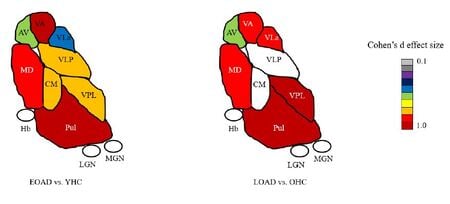

Most neuroimaging studies view the thalamus as a unitary structure, missing out on the specificity of thalamic nuclei and their role in disease. For e.g. Alzheimer's disease researchers have focused almost exclusively on the hippocampus even though the anterior thalamic nuclei is part of the limbic memory circuit (Papez circuit) responsible for episodic memory. We have shown thalamic nuclei atrophy in early MCI that even precedes hippocampal atrophy. This atrophy progressively increases with disease stage. We have recently published differences in early vs. late onset AD in thalamic nuclear atrophy (see image left). Our group has found similar nuclei specific atrophy in the ventral posterolateral nucleus (VPL) in alchohol use disorder, accompanied by concomitant disruption in functional connectivity. We have also demonstrated specific atrophy of thalamic nuclei close to the third ventricle (mediodorsal, pulvinar etc) in multiple sclerosis. We are currently examining thalamic nuclei involvement in familial AD, frontotemporal dementia (FTD), amyotrophic lateral sclerosis (ALS) and schizophrenia. Please see publications tab for specific papers.